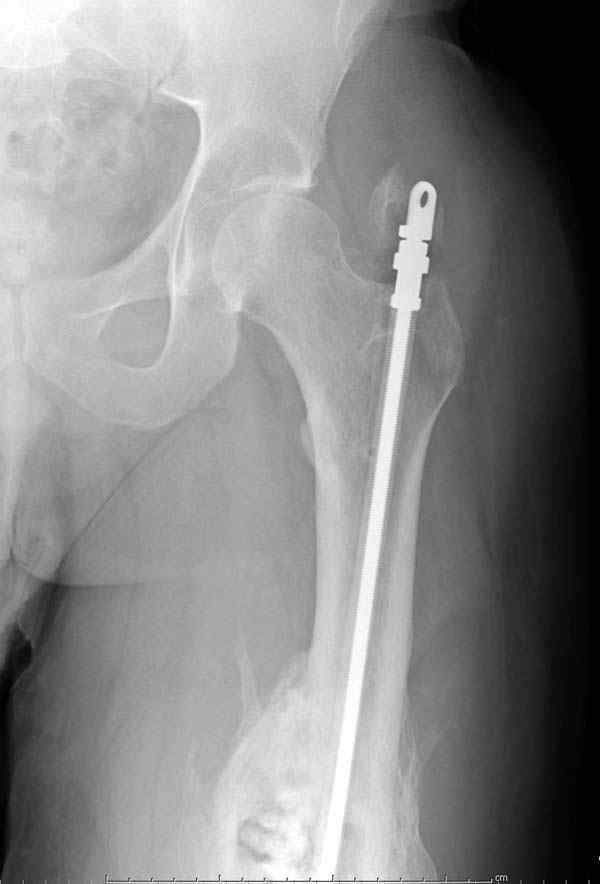

Через 3 года после травмы констатировало отсутствие консолидации бедренной кости, сохранение признаков хронического остеомиелита (свищ в нижней трети левого бедра). Произведен демонтаж аппарата, реостеосинтез бедренной кости спице-стержневым аппаратом, некрсеквестрэктомия. В аппарате удалось лишь частично произвестиустранение углообразной деформации бедренной кости [image 05] .